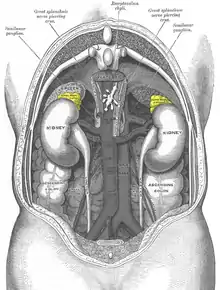

When a stressful situation is encountered, stress hormones are released into the blood stream. Adrenaline is released by the adrenal glands to begin the response in the body. Adrenaline acts as a catalyst for the fight-or-flight response,[11] which is a response of the sympathetic nervous system to encourage the body to react to the apparent stressor. This response causes an increase in heart-rate, blood pressure, and accelerated breathing. The kidneys release glucose, providing energy to combat or flee the stressor.[12] Blood is redirected to the brain and major muscle groups, diverted away from energy consuming bodily functions unrelated to survival at the present time.[11] There are three important axes, the adrenocorticotropic axis, the vasopressin axis and the thyroxine axis, which are responsible for the physiologic response to stress.

When a receptor within the body senses a stressor, a signal is sent to the anterior hypothalamus. At the reception of the signal, corticotrophin-releasing factor (CRF) acts on the anterior pituitary. The anterior pituitary in turn releases adrenocorticotropic hormone (ACTH).[13][14] ACTH induces the release of corticosteroids and aldosterone from the adrenal gland. These substances are the main factors responsible for the stress response in humans. Cortisol for example stimulates the mobilization of free fatty acids and proteins and the breakdown of amino acids, and increases serum glucose level and blood pressure,[12] among other effects.[15] On the other hand, aldosterone is responsible for water retention associated with stress. As a result of cells retaining sodium and eliminating potassium, water is retained and blood pressure is increased by increasing the blood volume.